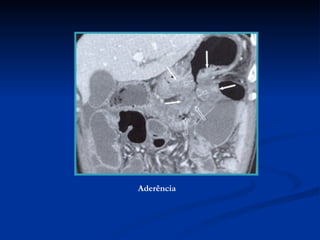

Aderência